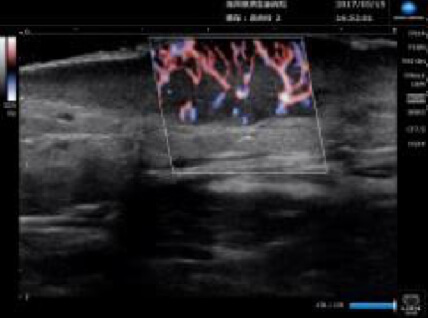

超音波診断装置

超音波を用いた皮下腫瘍の診断や、外傷時の皮下異物などの診断に役立ちます。視診、触診だけではわからない情報をたくさん得ることができます。患者さんは痛みもありませんので、子供さんでも検査を受けることができます。

コニカミノルタの超音波機器を導入しています。